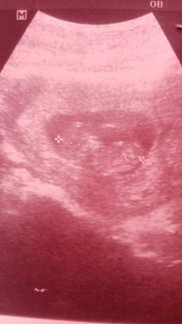

Apa yang korang nampak pada gambar ni ?

Doktor dah explain dan saya dah paham , tak ada masalah apa apa . kandungan dah masuk 10minggu . Cuma sekarang ni , saya masi takpandai nak tengok gambar scan macam ni , masih taktahu yang macam mana tengok . Maaf sekali lagi , buat keliru semua , Saya edit semula ayat yee . #firstmom #ingintahu